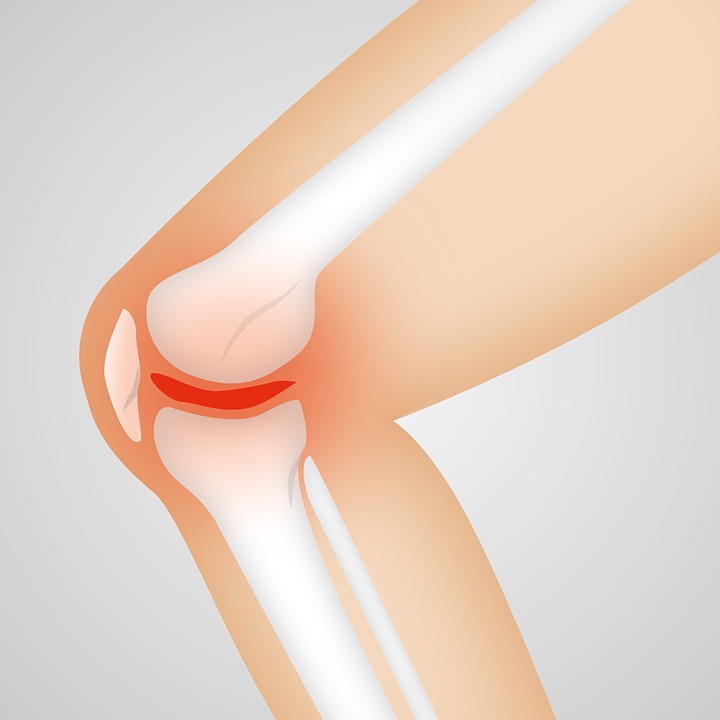

Az oszteoartritisz degeneratív ízületi betegség, az ízületi gyulladás leggyakoribb formája, ahol a porc a túlzott kopástól lebomlik, így a csontok egymáshoz dörzsölődnek mozgás közben, ami fájdalmat, merevséget és a térd megdagadását okozza.

Feltételezték, hogy a térd úgy viselkedik, mint a mérnöki szerkezetek: a sima és jól síkosított felületek hangtalanul mozdulnak el egymáson, a durva, kevéssé síkos felületek pedig hangot generálnak.

Megállapították, hogy minél több kiugrást jegyeztek fel a mikrofonok a hanghullámok rögzítésekor, vagyis minél “hangosabb” volt a térd, annál súlyosabb volt az oszteoartritisz.

Amikor a térd hallható hangot ad, például “kattog”, az is utalhat oszteoartritiszre.